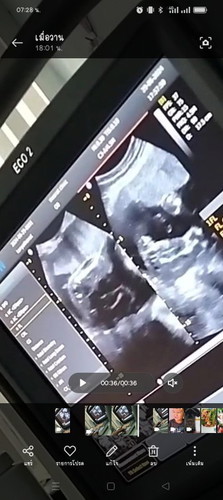

อยากให้แม่ๆช่วยดูเพศน้องน่อยค่ะ แม่ซาวด์ตอนอายุครรภ์ 24w หมอบอกกลีบชัดเลยนะคุณแม่ แต่แม่ดูไม่ออก เลยอยากให้แม่ๆช่วยดูอีกทีค่ะ

น่าจะเพศหญิงมั้ยค่ะ